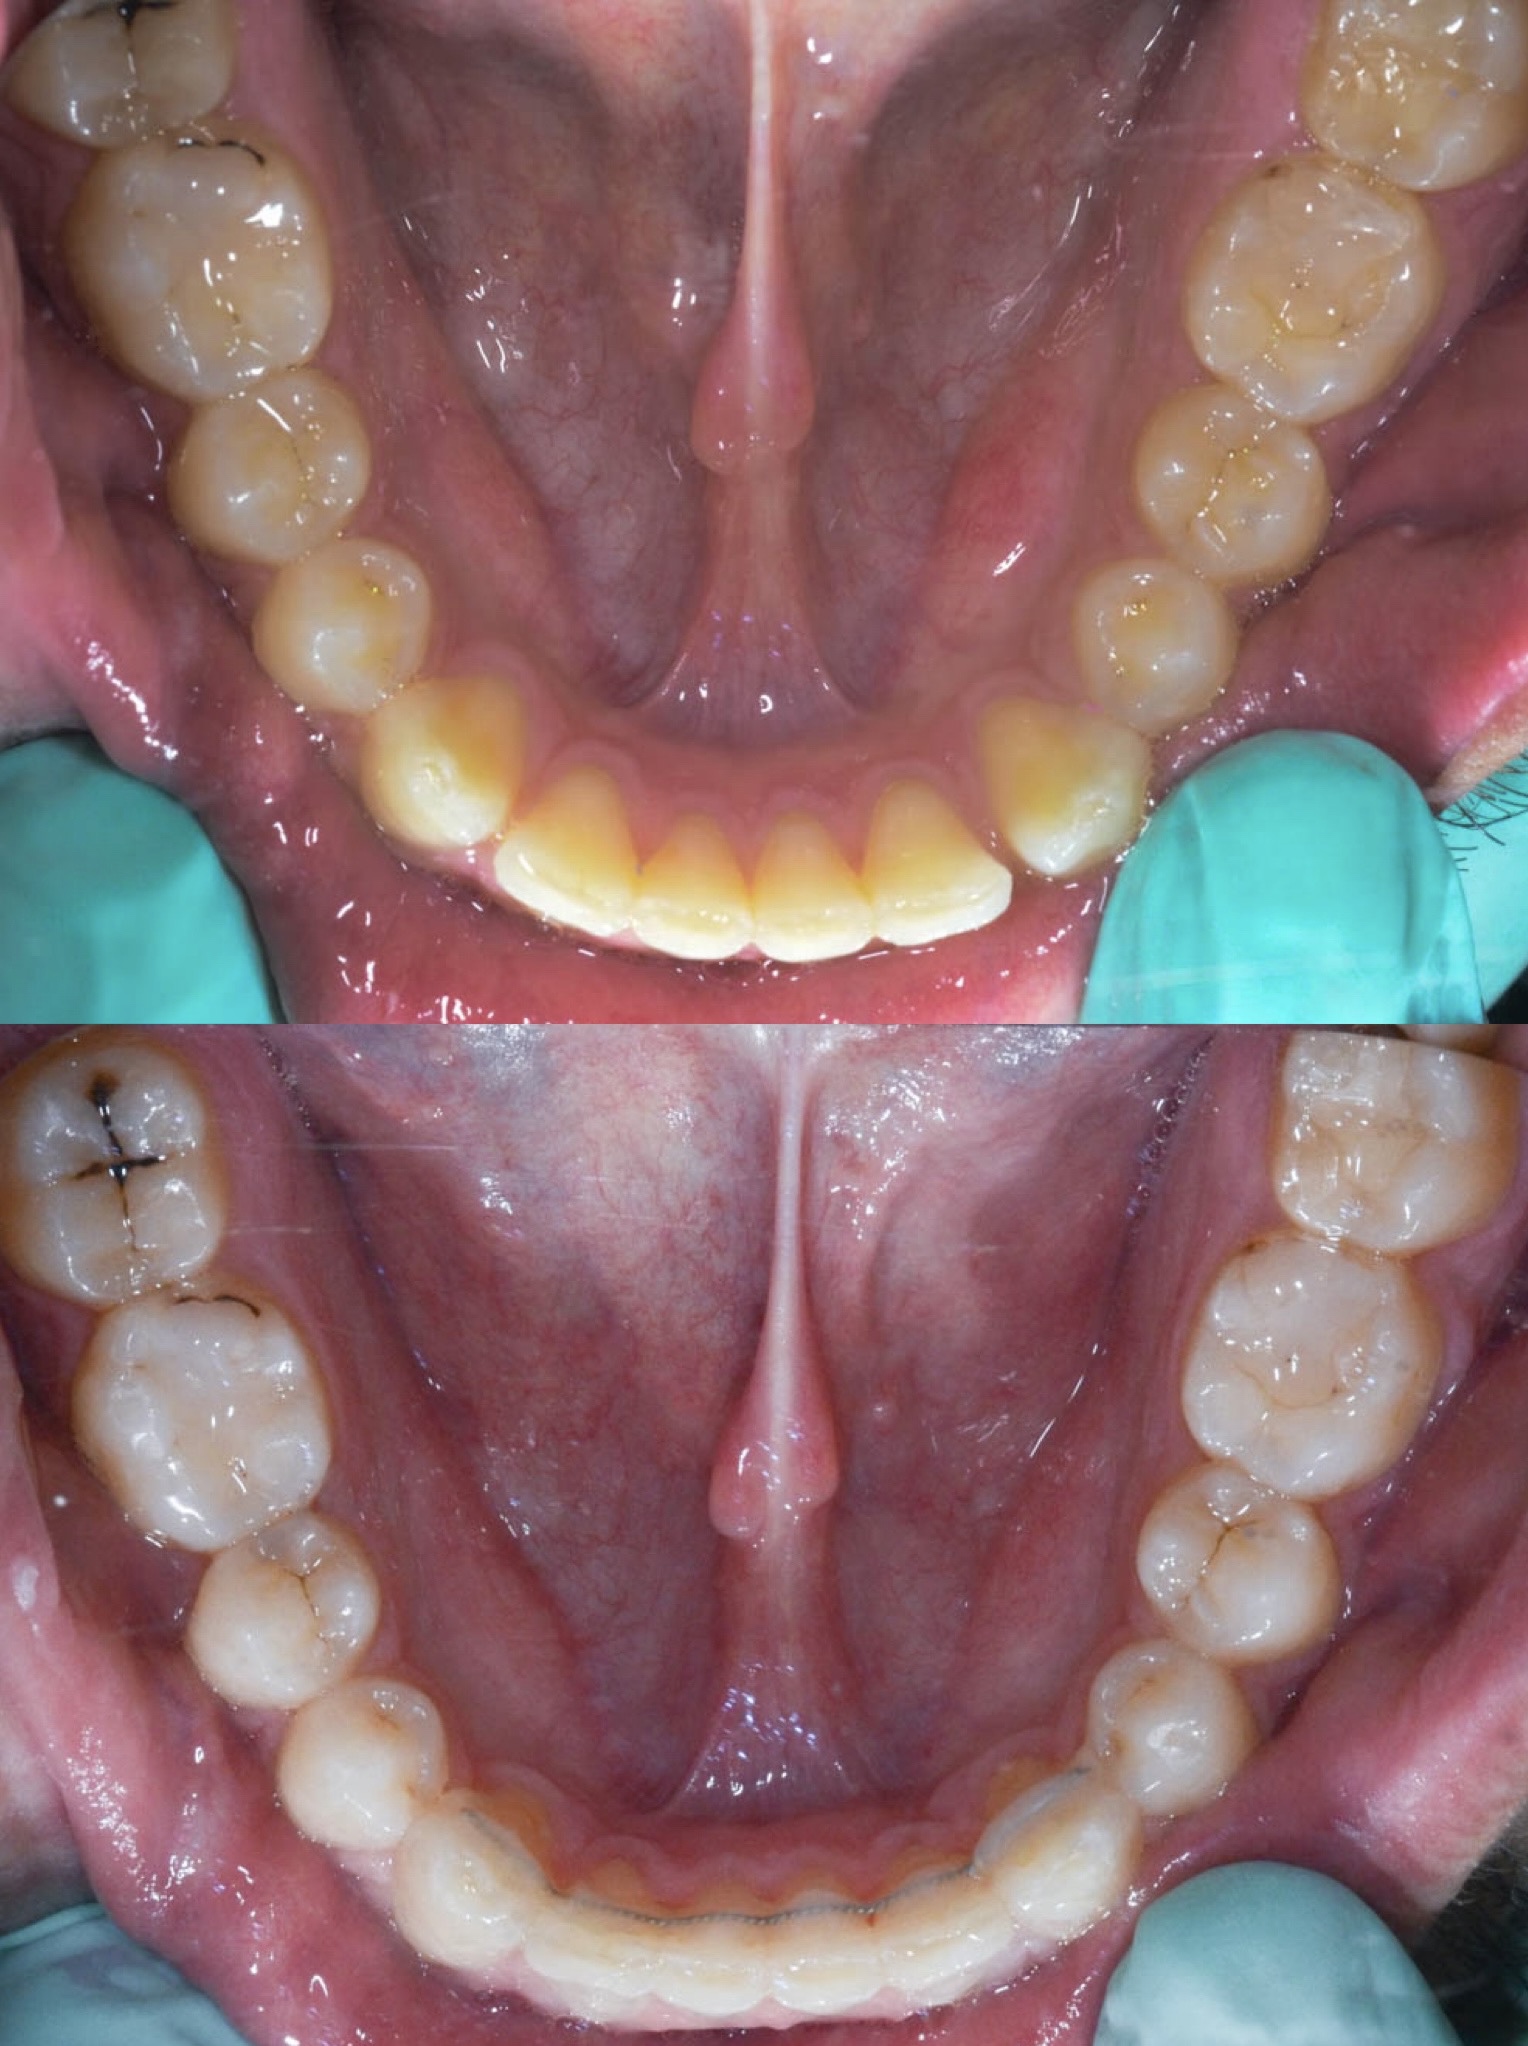

Slučaj 1: ispravljanje otvorenog zagriza i kompresije Invisalign full terapijom

Slučaj 2: ispravljanje kompresije Invisalign full terapijom- u ovom slučaju je izvađen jedan donji sjekutić

Slučaj 3: ispravljanje kompresije Invisalign full terapijom

Slučaj 4: ispravljanje kompresije Invisalign full terapijom

Slučaj 5: ispravljanje kompresije i križnog zagriza Invisalign full terapijom

Slučaj 6: ispravljanje kompresije i dubokog zagriza Invisalign full terapijom

Slučaj 7: ortodontska predprotetska terapija Invisalign full